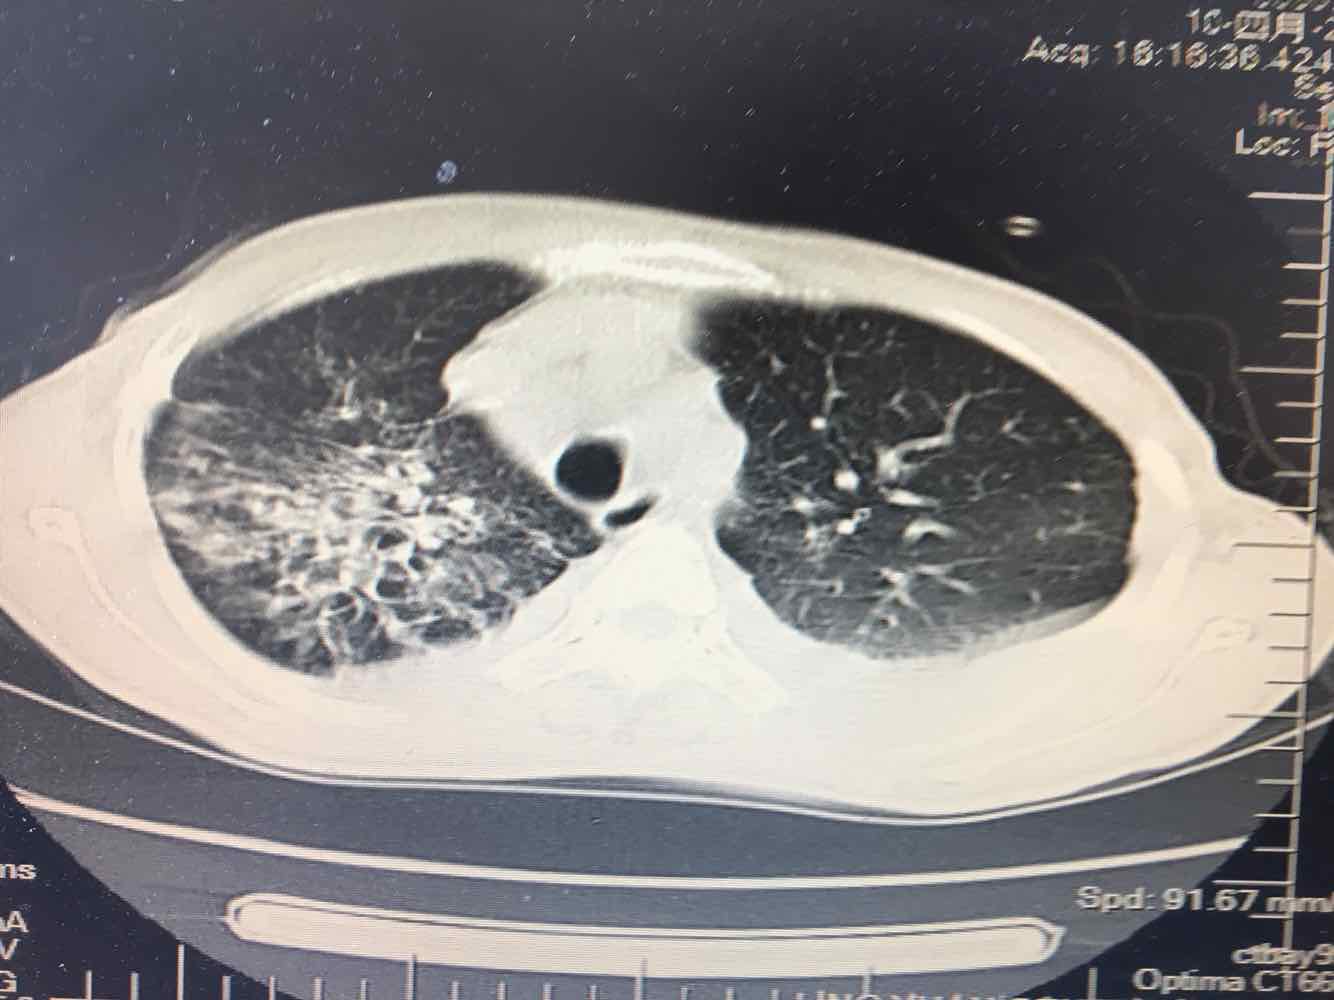

女,51岁,支气管扩张病史多年。慢性咳嗽咳痰喘息30年,加重1个月,无发热,气短为主,痰液不多,上腹不适,少尿。双肺干湿罗音。